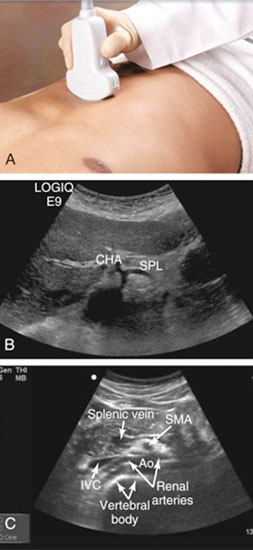

ترنسدوسر سونوگرافی رو باید عمود بر شکم بیمار بگیریم و اگه مایل بگیریم قطری ک بهمون نشون میده دقیق نیست

ترنسدوسر سونوگرافی رو باید در هر دو حالت طولی و عرضی قرار بدیم و آئورت رو ارزیابی بکنیم

ابتدای آئورت شکمی بیمار رو اگه بخوایم ببینیم سر ترنسدوسر رو در قسمت زاویه دنده ای وسط شکم بیمار قرار میدیم و مارکر ترنسدوسر به سمت راست مریض قرار میگیره

دو شاخه اصلی ک زودتر از آئورت جدا میشن شامل تنه سلیاک(که خودش به دو شاخه شریان هپاتیک و شریان طحالی تبدیل میشه) و شریان مزانتریک فوقانی هستن

(در تصویر A مارکر ترنسدوسر به سمت راست بیماره)

CHA : Common hepatic artery

SPL : Splenic artery

SMA : Superior mesentric artery

Ao : Aort

IVC : Inferior vena cava